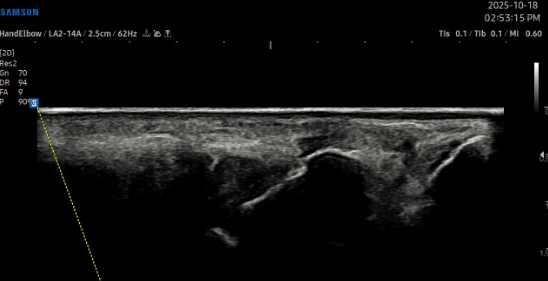

치료 전 (TFCC)

치료 후 (TFCC)\

- 치료기간 : 25 . 8 . 5 ~ 25 . 10 . 28

- 치료횟수 : 4 cycle(20) 회